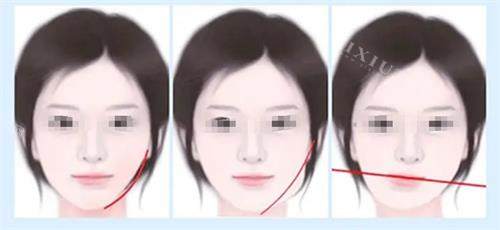

何锦泉医生是广州广大口腔医院的颌面整形医师,拥有丰富的正颌手术经验。他专注于骨性地包天、凸嘴、偏颌等复杂颌面畸形的矫正,尤其擅长运用3D导板技术进行精细手术。3D导板技术通过术前CT扫描建模,模拟截骨范围和骨骼移动轨迹,误差可控制在0.1毫米以内。这种技术不仅提高了手术的精细度,还降低了术后并发症的风险。

何锦泉医生为张先生进行了详细的面部检查和三维模型分析,发现其凸嘴主要是由于上颌骨前突所致。于是,何医生制定了上颌骨后移的手术方案,并结合3D导板技术进行精细定位。

广州广大口腔医院凭借其新型的3D导板技术和何锦泉医生的正规技能,在正颌手术领域取得了显著的成效。无论是骨性凸嘴、地包天还是面部不对称,广大口腔都能为患者提供个性化的解决方案,帮助他们重获自信的笑容。